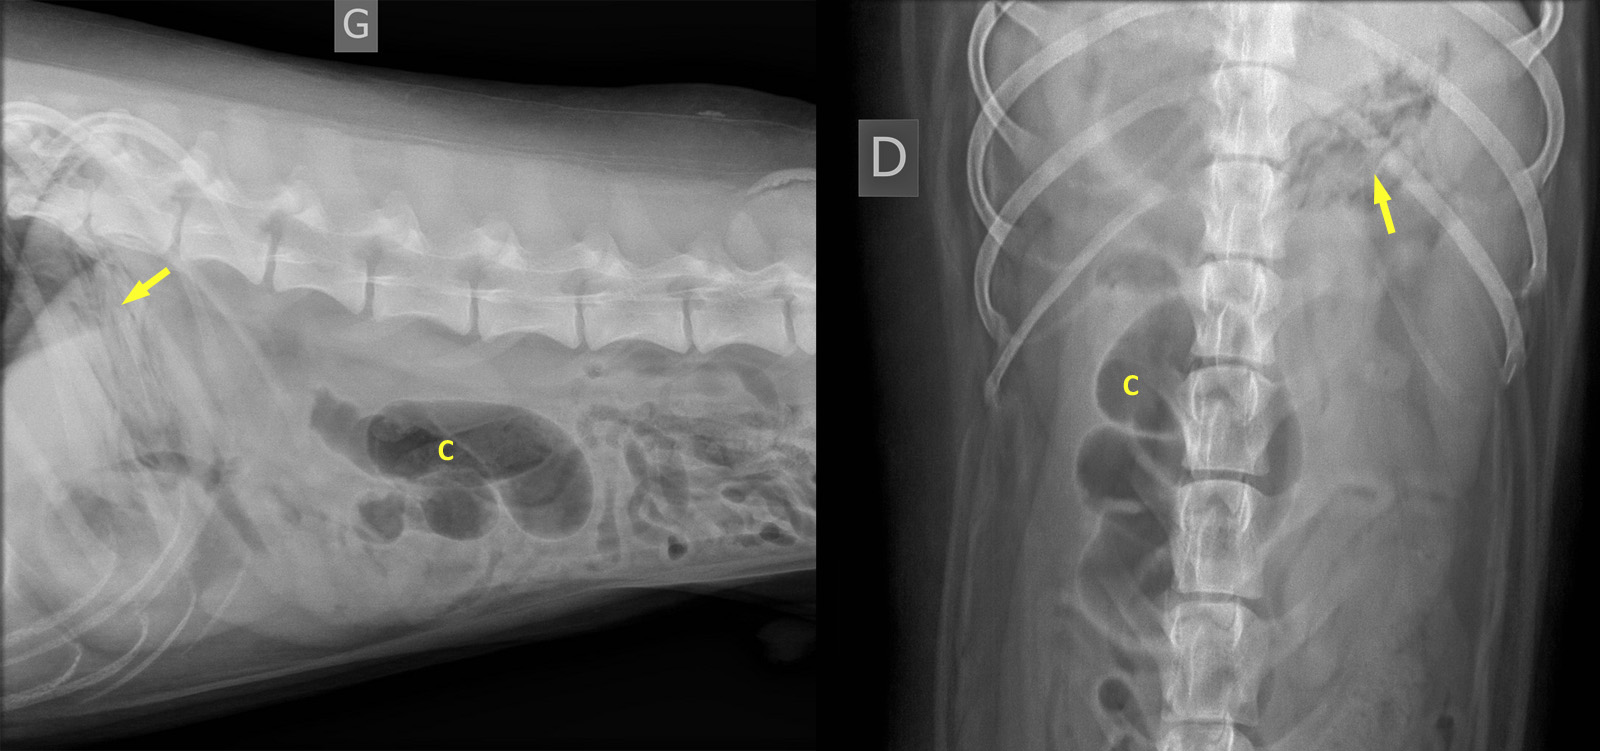

Sur ces radiographies, ce qu’il fallait reconnaître est la série de lignes d’opacité tissulaire à minérale à l’intérieur du fondus gastrique (flèches). Outre le fait que l’antre pylorique comportait un peu de gaz, il n’y avait pas de réel signe d’obstruction. Le détail abdominal était relativement bon et le duodénum n’était pas anormalement dilaté, ce qui n’exclut pas la possibilité de pancréatite, mais du moins, aucun signe radiographique suggérait cette possibilité. Le petit intestin ne comportait pas une quantité anormale de liquide ou d’air. Le segment rempli d’air (C) au centre-droit de l’abdomen avait la forme et la position du cécum et d’une portion du côlon. Lors de volvulus intestinal, on s’attend normalement à observer une dilatation intestinale marquée et de l’épanchement péritonéal, ce qui n’était pas le cas. Une échographie s’imposait alors pour aller vérifier l’estomac et exclure plus définitivement la possibilité de corps étranger intestinal ou de pancréatite.